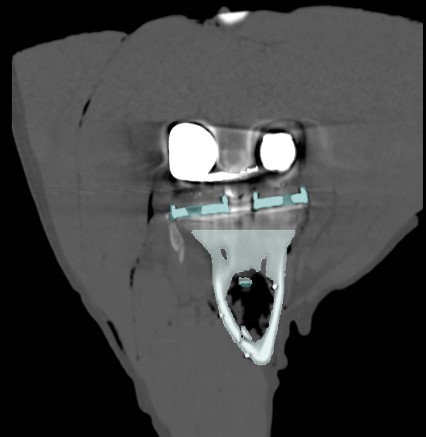

Adequate fixation of a revision (knee)implant is crucial for its survival. However, this is challenging due to bone loss and poorer quality of the remaining bone. By preoperatively examining the anatomy, reason for revision, and the amount and quality of bone before surgery, a tailored treatment can be developed to ensure proper fixation. The use of 3D CT-based migration analysis can help determine whether the fixation is adequate.